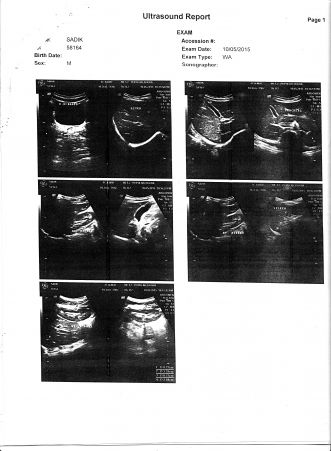

প্রেসক্রিপশন, রিপোর্ট . . .